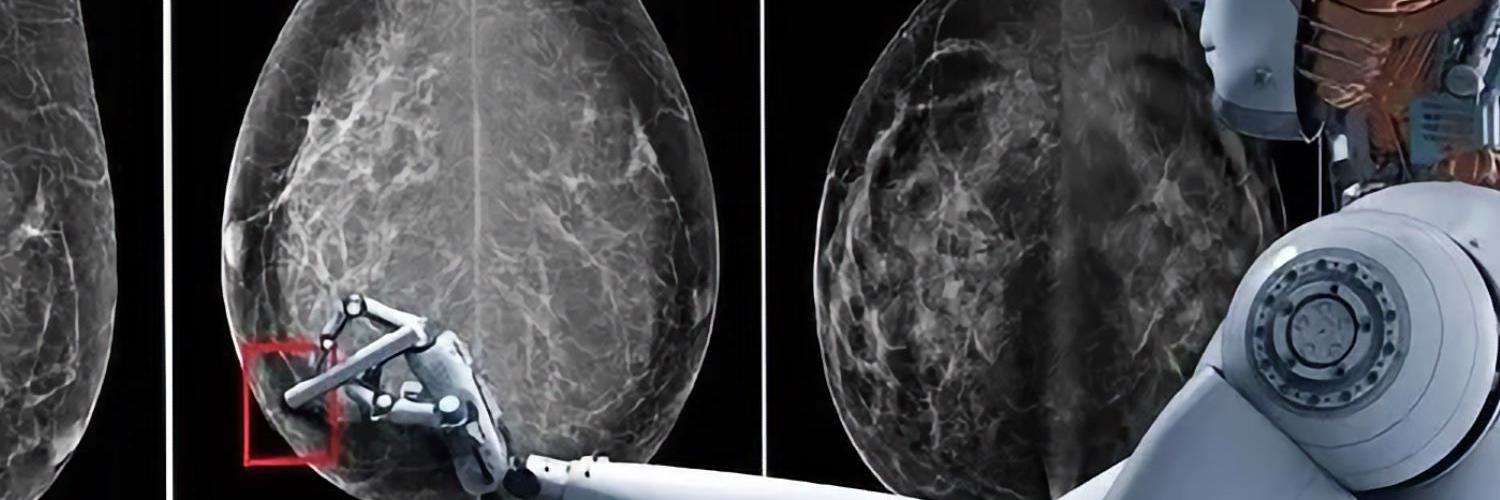

Einsatz von künstlicher Intelligenz

Hier kommt im Radiologischen Zentrum nun neuerdings künstliche Intelligenz zum Einsatz. Nach dem Motto "Vier Augen sehen mehr als zwei" werden die Aufnahmen auch von einer künstlichen Intelligenz beurteilt und dabei erkannte auffällige Befunde werden kenntlich gemacht. Letztlich entscheidet aber die Radiologin oder der Radiologe, die/der weitere Informationen aus der Vorgeschichte, den Tastbefund und die Ultraschalluntersuchung einbeziehen kann.

KI Software

Die von uns verwendete KI Software stammt von der Schweizer Firma b-rayZ AG. Sie wurde an tausenden von Mammographien mit gesicherten Befunden "angelernt" (Machine Learning). Die Software wird im Rahmen des Qualitätsprogramms QuaMaDi eingesetzt, kommt aber bei uns auch Patientinnen zugute, die nicht an QuaMaDi teilnehmen (können).